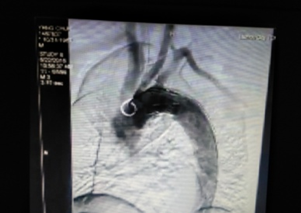

近日,我院成功開(kāi)展了一例主動(dòng)脈夾層腔內(nèi)修復(fù)術(shù)。此項(xiàng)技術(shù)的開(kāi)展為大動(dòng)脈疾病患者帶來(lái)福音,也標(biāo)志著我院在血管疾病介入治療方面提升到新的水平。?危險(xiǎn):兇猛“血管殺手”嚴(yán)重威脅健康60多歲的李大爺(化名),結(jié)腸腫瘤入院,完善相關(guān)檢查后確診為主動(dòng)脈夾層。主動(dòng)脈夾層是災(zāi)難性的血管疾病,堪稱(chēng)“血管殺手”,如不及時(shí)...